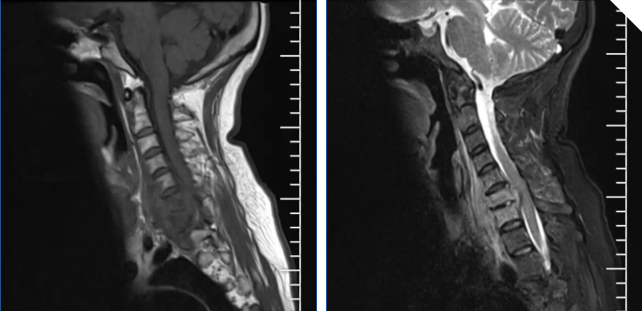

术前核磁片

为求进一步治疗,2025年8月底李阿姨经好友介绍来到萍乡市第二人民医院。入院查体时,腰背部有一处4*3cm的结痂创口且已愈合,但颈椎棘突存在明显压痛与叩击痛,颈部活动因疼痛受到限制。更令人担忧的是,检查发现李阿姨双上肢部分区域皮肤感觉变迟钝,肌肉力量减弱,同时双上肢深反射明显亢进,且霍夫曼征阳性,提示脊髓及神经功能受到明显影响。结合病史和后续完善的相关检查,脊柱外科团队初步诊断李阿姨因皮肤溃疡诱发“化脓性脊柱炎”,不仅存在颈椎椎体及椎间盘破坏性改变,颈椎椎管内脓肿占位压迫颈部脊髓导致“不全瘫”等严重问题,同时伴有心包积液、冠心病、贫血等基础病症,这一系列复杂的病情给临床诊疗带来了不小的挑战。

患者当时的情况十分危急,若不及时干预,极有可能发展为完全性瘫痪,出现永久性神经功能损害,严重影响预后。“病情就是战情”,面对紧急状况,脊柱外科团队迅速组织病例讨论,结合患者的病史、检查结果及病情变化,判断化脓性脊柱感染的病灶区已对脊髓造成严重压迫和炎性侵袭,必须尽快通过手术“清除感染病灶、解除神经压迫、重建颈椎稳定性”,才能遏制病情进展。